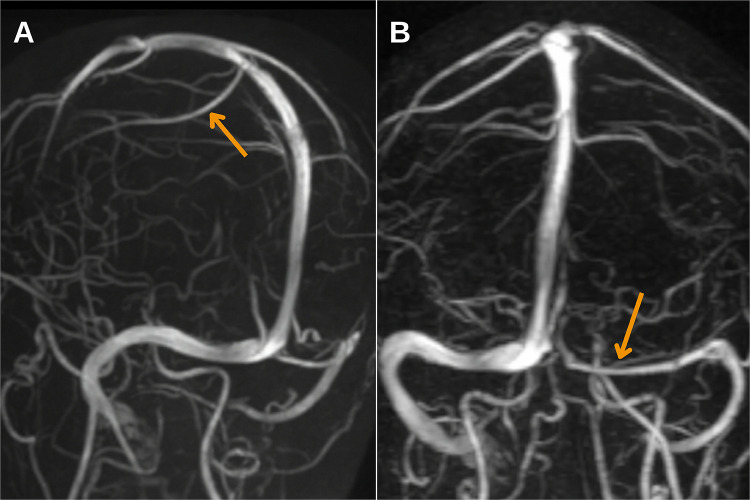

Case presentation: We present a rare case of cerebral infarction as a complication of retrograde cerebral venous air embolism following haemodialysis catheter removal in a young patient, with management leading to a favourable outcome. The diagnosis was confirmed based on clinical manifestations and neuroimaging findings, with air emboli identified in the subarachnoid space on the CT scan, followed by characteristic MRI changes defined for cerebral air embolism infarcts. Timely diagnosis allowed for the rapid initiation of hyperbaric oxygen therapy and the rehabilitation process, resulting in positive outcomes.

Conclusion: Timely neuroimaging-particularly CT within the first 2 hours-is critical for diagnosing CAEI. MRI findings, including cytotoxic and vasogenic oedema in a distal vascular distribution and leptomeningeal enhancement, further support diagnosis. Early identification and treatment initiation are essential for improving patient outcomes.